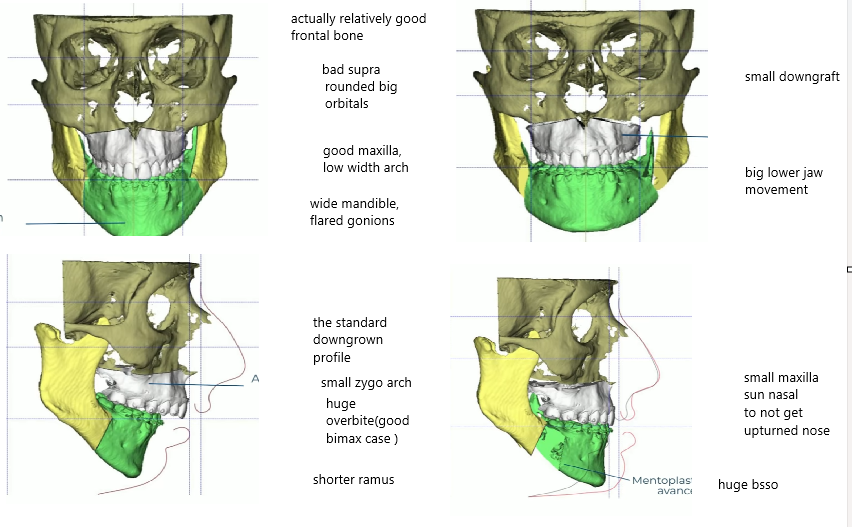

Lets look at the standard recessed case, which has a functional issue. But he doesnt have a gummy smile or much short face syndrome. This makes his front appear the same almost. As we also can notice is that more forward projection will make it seem like its less width on the mandible because of perception.

huge side ascension:

almost nothing changed from front because of no sfs or excess gummy show:

lets look at the bones:

Lets look at the standard recessed case, which has a functional issue. But he doesnt have a gummy smile or much short face syndrome. This makes his front appear the same almost. As we also can notice is that more forward projection will make it seem like its less width on the mandible because of perception.

huge side ascension:

almost nothing changed from front because of no sfs or excess gummy show:

lets look at the bones: